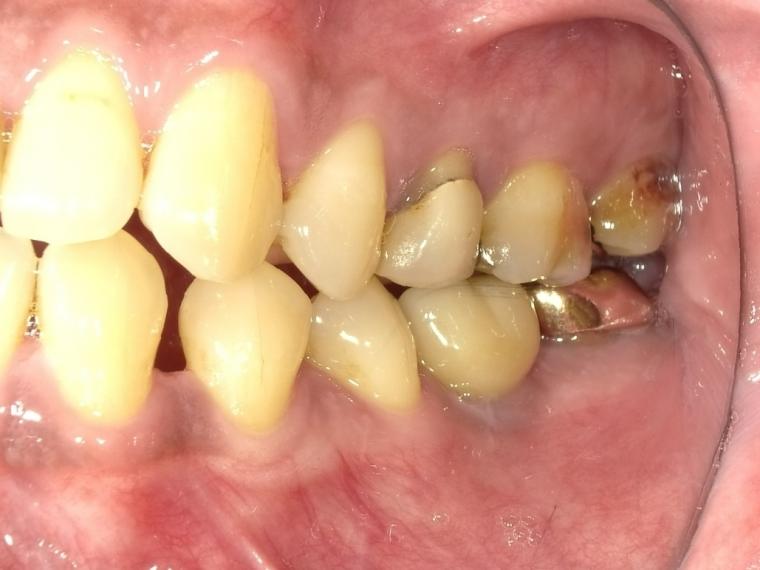

BEFORE

44歳男性

/下顎1本欠損/インプラント埋込手術

他院で左下第一大臼歯を治療していましたが、治療を中断してしまい、状態が悪化、抜歯になった患者さんです。